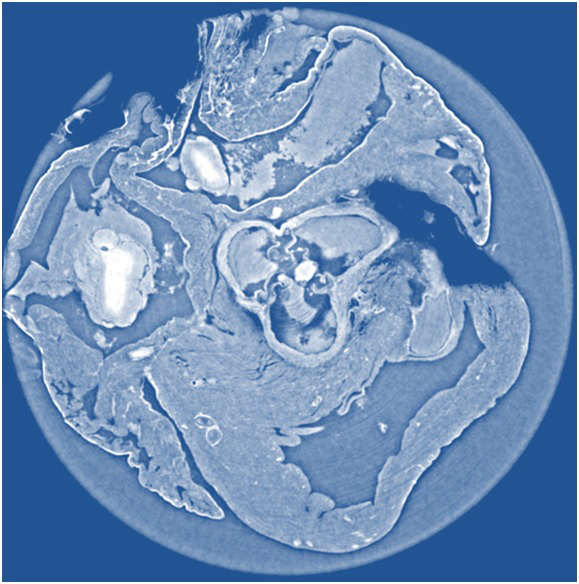

To answer this question, a large group of researchers in Europe set out to compare three different X-ray phase tomography methods at the European Synchrotron Radiation Facility’s (ESRF) beamline ID19 in France—X-ray grating interferometry, propagation-based phase tomography with single-distance phase reconstruction, and holotomography.

Led by Irene Zanette, a scientist affiliated with both ESRF and the Technische Universität München (TUM) in Germany, the researchers put these three techniques to the test by examining cancerous tissue from a mouse model and an entire rat’s heart, which they report this week in the Journal of Applied Physics, from AIP Publishing.

So what did they find by comparing methods? The group was able to show that for each specimen, the spatial resolution derived from the characteristic morphological features is about twice as good for holotomography and single-distance phase reconstruction compared to X-ray grating interferometry. They also found that X-ray grating interferometry data generally provide much better contrast-to-noise ratios for anatomical features, excel in fidelity of the density measurements, and are more robust against low-frequency artifacts than holotomography.